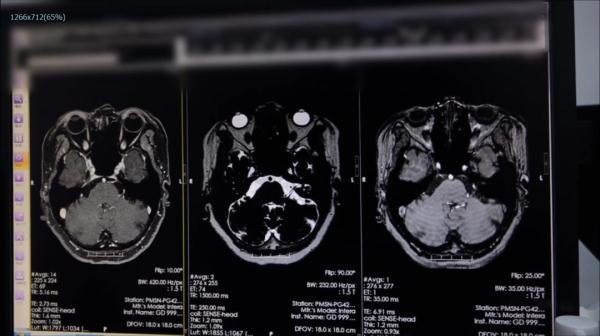

后来做进一步检查时

医生发现陈姨脑室多发异常信号

怀疑可能是脑肿瘤引起

经过检查,医生最终确认

陈姨患的是面肌痉挛